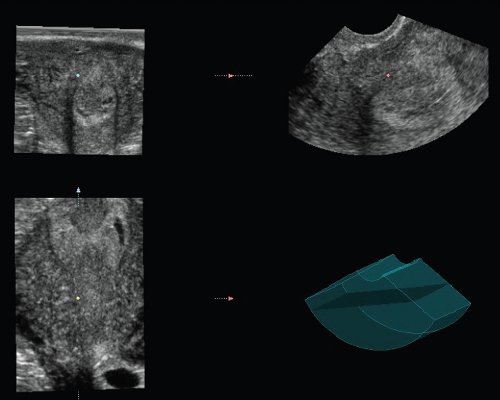

Шейка матки обычных размеров. Цервикальный канал локально расширен. В цервикальном канале лоцируется кистозная полость средним диаметром 8 мм. Внутри полости определяется кистозное включение диаметром 2 мм (рис. 1, 2).

Рис. 1. Фронтальный срез поверхности полости матки и шейки.

Рис. 2. Сагиттальный срез полости и шейки матки.

Область придатков была тщательно исследована с целью выявления возможной внематочной беременности. Далее было проведено трехмерное мультипланарное исследование матки и шейки. Забор объема производился методом "свободной руки". Кроме того, выполнено исследование в режиме поверхностной реконструкции.

Рис. 3. Мультипланарная реконструкция полости и шейки матки.

Рис. 4. Мультипланарная реконструкция шейки матки.

Рис. 5. Поверхностная реконструкция плодного яйца в шейке матки.

Кистозное образование в шейке было идентифицировано как плодное яйцо с желточным мешком. Эмбрион не определяется (рис. 3-5). Симптом "скольжения" отрицательный.

Наличие анэхогенной жидкости в полости матки, по нашему мнению, является характерным признаком, сопутствующим малому сроку беременности. В эпоху трансабдоминальных исследований этот признак интерпретировался как "ложное" плодное яйцо (рис. 6).

Рис. 6. Мультипланарная и поверхностная реконструкция полости и шейки матки.